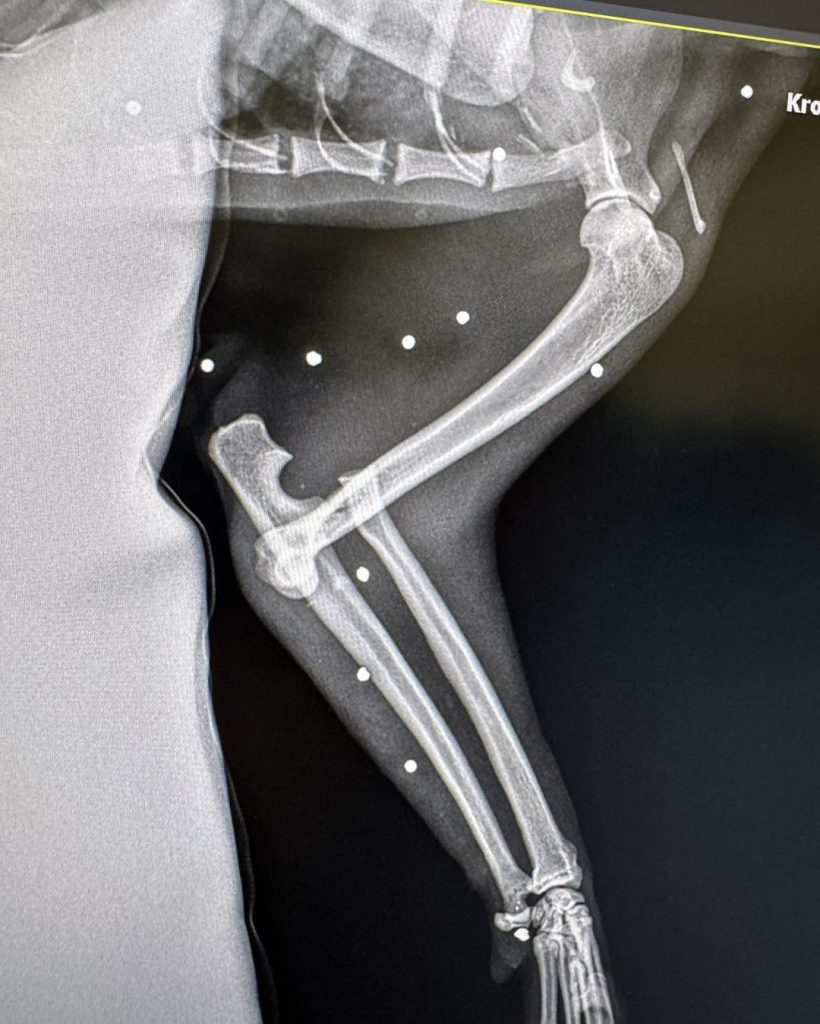

Pod opiekę Nyskiego Pogotowia Opiekuńczo – Adopcyjnego dla Zwierząt Łapa trafił w środę ranny kotek. Zwierzę trafiło pod opiekę specjalistów z podejrzenim zwichnięcia stawu łokciowego miało uraz przedniej kończyny. Po wykoanniu zdjęć RTG okazało się, że to nie jedyny uraz zwierzęcia. W głowie, jamie brzusznej o klatce piersiowej odkryto ponad 30 śrucin.

– Dziś pod naszą opiekę trafił kot, u którego doszło do zwichnięcia stawu łokciowego z towarzyszącym przemieszczeniem kości łokciowej, najprawdopodobniej na skutek ludzkiego okrucieństwa! Zdjęcia RTG wykazały nie tylko uraz przedniej łapy, ale również obecność w ciele kota ponad 30 kulek śrutu! Kim trzeba być? Żeby zrobić sobie ze zwierzęcia żywą tarczę!? Na usta cisną się same najgorsze słowa! – piszą na swojej profilu na facebooku Animalsi z Nyskiej ŁAPY.

Badania diagnostyczne wykazały u kota silny stan zapalny, w trybie pilnym trafił na stół operacyjny w celu ratowania przedniej łapy. Następnie zwierze czekają kolejne zabiegi mające na celu usunięcie śrutu z ciała.